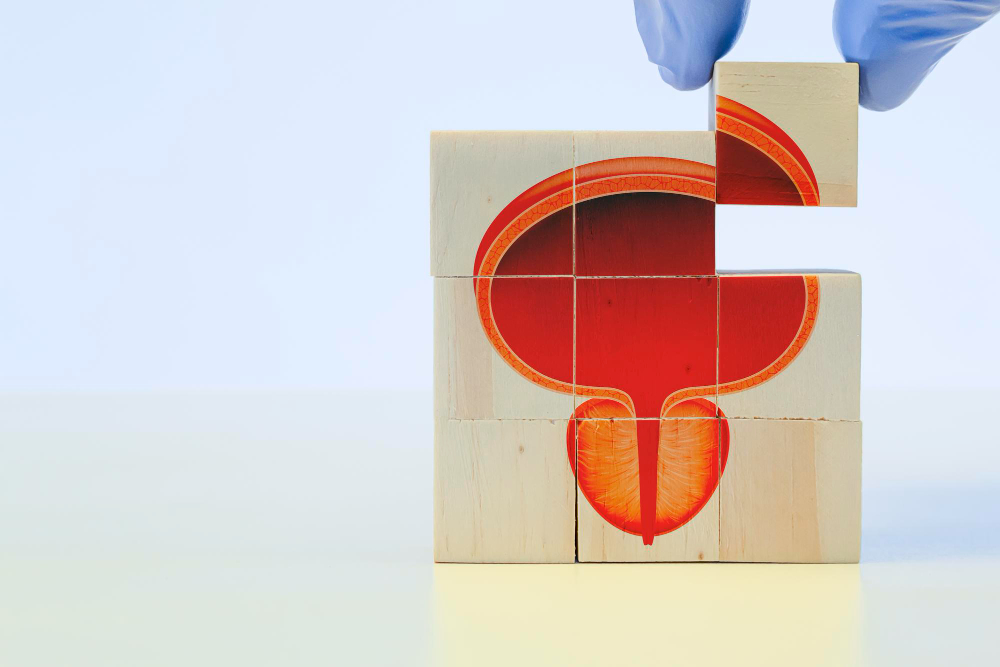

הערמונית, מזכירה בצורתה את הערמון מכאן שמה בעברית, ממוקמת מתחת לשלפוחית השתן וסובבת את השופכה, אשר עוברת דרכה. לכן, כאשר הערמונית גדלה – היא עלולה ללחוץ על השופכה ולגרום לקשיים בהתרוקנות, זרם שתן חלש, לצורך תכוף במתן שתן, להטלת שתן לילית, ומאידך אף לעצירת שתן מוחלטת או לזיהומים חוזרים. אמנם מדובר בבעיה שאינה מסכנת חיים, אך היא עשויה להשפיע רבות על התפקוד היומיומי, על איכות השינה, ועל איכות החיים האישית של המטופל.

בלוטת הערמונית ממוקמת כאמור מתחת לשלפוחית השתן והשופכה עוברת דרך בלוטה זו. במהלך החיים, במיוחד מגיל 50 ואילך, הערמונית נוטה לגדול. מדובר בתהליך טבעי הקשור לשינויים הורמונליים – בעיקר ברמות הטסטוסטרון והדיהידרוטסטוסטרון (DHT). ההגדלה גורמת ללחץ על השופכה ולפגיעה בזרימת השתן. מדובר בבעיה שאינה ממארת, אך בעלת השפעה ניכרת על איכות החיים. נתונים עדכניים מצביעים על כך שכ־50% מהגברים בגיל 60 סובלים מהגדלה שפירה של הערמונית, ובגיל 80 – למעלה מ־80% מהגברים מושפעים ממנה.

האבחנה כוללת שילוב של שאלון תסמינים, בדיקה גופנית, בדיקות דם לרמת PSA (לשלילת סרטן), סונר (אולטרסאונד) כולל שארית שתן, ולעיתים בדיקת זרימת שתן (Uroflowmetry).